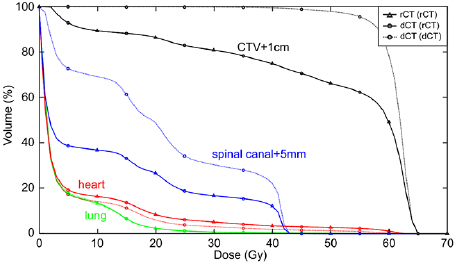

Standard image High-resolution imageA comparison of the rCT gold standard DVH with dCT DVHs using both directly outlined rCT structures and deformed pCT structures is shown at figure 9.

Figure 9. Gold standard rCT DVH overlaid with dCT DVHs calculated using either directly outlined rCT structures 'dCT (rCT)' or deformed pCT structures 'dCT (dCT)' for a single patient. The dCT (rCT) matches the rCT DVH well, whereas the dCT (dCT) is noticeably different for all structures with the exception of the lungs. It should be noted that spinal canal + 5 mm differences are largely attributable to outlining differences—the rCT structure extends further than the pCT (and hence the deformed) structure in both the superior and inferior directions. However, this is not an issue as only Dmax is considered for serial structures such as this.

Download figure:

Standard image High-resolution imageDemonstration of clinical application